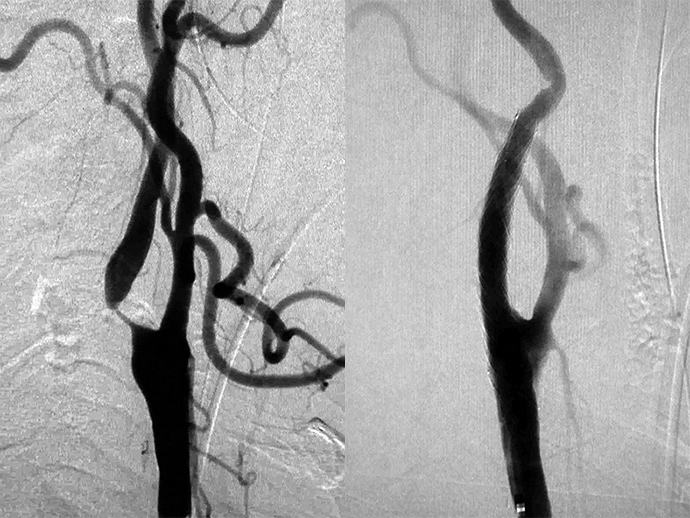

超音波検査でクローン病がわかりますか?

超音波は、音波を使用して胃腸管の画像を生成する、放射線を使用しないタイプの画像処理です。また、次のような他の臓器の健康上の合併症を特定するのにも役立ちます。

超音波は周囲のクローン病の炎症を正確に特定できます

著作権 © 2016 Rune Wilkens et al. CC BY 4.0